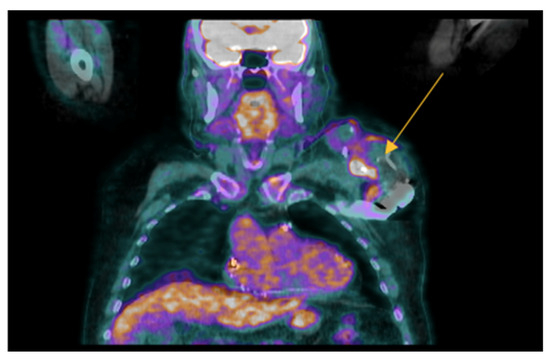

- Identifying infections within the heart: this includes detecting infections in native valves, prosthetic valves, and implanted cardiac devices. Performance varies depending on the location: sensitivity is low for native valve infections and for infections involving cardiac device leads. Sensitivity is significantly higher for prosthetic valve infections and infections within cardiac device pockets. Specificity remains high across all these scenarios;

- Uncovering hidden infectious spread: FDG-PET/CT can also detect clinically silent disseminated infectious disease, identifying primary infection source, and/or septic embolism, which can be crucial for diagnosis and guiding patient management.